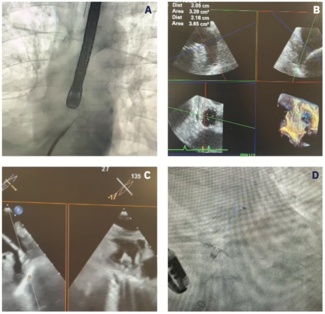

Drs Mohan and Bradley highlight strategies for left atrial appendage closure implantation at 2 metropolitan Detroit institutions, discussing how care is delivered at each institution.